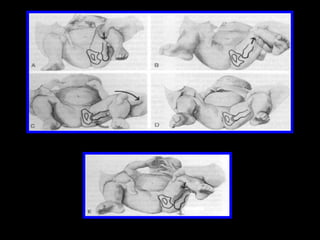

Tratamiento para Coxa Vara El consenso general para el tratamiento sintomático o progresiva congénita Coxa Vara es con cirugía.  La cirugía permite la reconstrucción del cuello eje angular para lograr una más normal y equilibrada estructura.  Algunos recomiendan que en los casos en que la cirugía es necesaria, que se realice , mientras que el niño es aún menor de edad y no como muchos creen que hay una mayor oportunidad para la articulación de la cadera a remodelar por completo con la nueva estructura de conjunto.

Terapia Conservadora: la desviación prácticamente no puede resolverse mediante métodos conservadores. b) Quirúrgica : - osteotomía correctora intertrocanterea valgizante, - si también existe una reducción de la torsión anterior, se lleva a cabo osteotomía rotativa y valgizante.

Tratamiento para CoxaVara El consenso general para el tratamiento sintomático o progresiva congénita Coxa Vara es con cirugía. La cirugía permite la reconstrucción del cuello eje angular para lograr una más normal y equilibrada estructura. Algunos recomiendan que en los casos en que la cirugía es necesaria, que se realice , mientras que el niño es aún menor de edad y no como muchos creen que hay una mayor oportunidad para la articulación de la cadera a remodelar por completo con la nueva estructura de conjunto.

Terapia Conservadora: ladesviación prácticamente no puede resolverse mediante métodos conservadores. b) Quirúrgica : - osteotomía correctora intertrocanterea valgizante, - si también existe una reducción de la torsión anterior, se lleva a cabo osteotomía rotativa y valgizante.